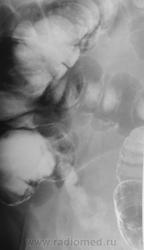

Такое ощущение, что слепая до конца не заполнилась. По-моему, я выставлял этот случай на сайте, но уж очень похоже. Никакими усилиями не возможно было заполнить слепую, хотя подозрения были. Только после т.н. опорожнения барий заполнил раковый канал.

Вполне может быть рак слепой кишки.

Согласен: купол слепой кишки выглядит ненормально, но возможно в результате операции. Вообще-то для большей ясности полагается контрастировать терминальный отд. подвздошной кишки. А колоноскопия здесь помогает не всегда.

ИМХО: слепая заполнена т.к. чётко видно обмазнный контрастом купол слепой кишки. Жаль, что не представлены R- граммы всех отделов толстой кишки.Показана фиброколоноскопия. При её безуспешности- РКТ брюшной полости, как компромиссный вариант УЗИ брюшной полости, для исключения синдрома поражения полого органа.